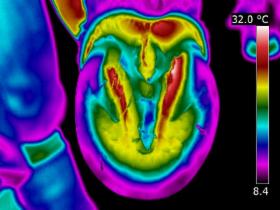

| DISTAL LIMB

| Thermography can point to potential conditions through changes in heat patterns, before the horse shows any clinical signs of injury. It can also reveal hidden signs that other diagnostic tools cannot. It gives us information we didn't know, we didn't know.

| | |  | | | I am very interested in the distal limb and thermography can be used to provide

you and your professional team additional information about conditions such as navicular syndrome,

laminitis, abscesses and corns. Importantly, it can give us information regarding hoof balance and weight-bearing. Hoof balance, often over looked, is a significant influence in the cause of lameness problems not only locally in the foot but throughout the musculature of the body through compensatory issues.